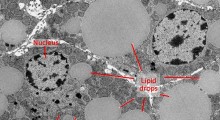

L'urea e l'ammoniaca nel cervello sono prodotti della degradazione metabolica delle proteine. L'urea è più conosciuta come il composto che viene secreto dal corpo nelle urine. Se l'urea e l'ammoniaca si accumulano nel corpo, ad esempio perché i reni non sono in grado di eliminarli, possono verificarsi sintomi gravi.

Il team ha utilizzato cervelli umani, donati dalle famiglie per la ricerca medica, e pecore transgeniche in Australia. I membri del team di Manchester hanno usato la spettrometria di massa con cromatografia a gas, una tecnica di avanguardia, per misurare i livelli di urea cerebrale. Perché i livelli siano tossici l'urea deve aumentare di 4 volte o più rispetto al cervello normale, dice il professor Cooper.